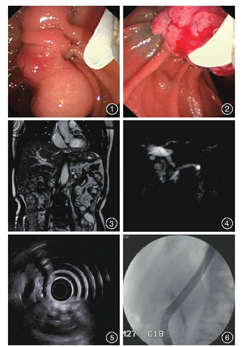

患者男,73岁,主因"反复腹痛、腹胀3年,加重2个月"入院。3年前因"十二指肠球部息肉"在我院行十二指肠息肉切除术及ERCP下胰管支架置入术。术中十二指肠乳头肿大(图1),可见分叶状肿物(图2)。术中选择性胆管造影及胰管造影后沿导丝置入7 Fr×9 cm胰管支架,置入鼻胆引流管至肝总管,胆汁流出通畅,过程顺利。病理结果提示:十二指肠乳头小肠绒毛管状腺瘤。术后3个月于我院ERCP下取出胰管支架。而后患者间断3次出现腹痛、腹胀,内科对症处理后可缓解。近2个月再次出现上腹部绞痛,腹胀,有加重趋势,性质同前,于当地医院行超声检查示:"胰管扩张,内多发性结石"。体重2个月下降10 kg。既往高血压病史30余年,9年前行左肾切除术。辅助检查:CA19-9 39.05 U/mL。腹部超声:肝囊肿,胰管增宽,胰管内多发强回声,左肾切除术后,右肾强回声,右肾囊肿。MRCP:胆总管中上段增宽(图3),主胰管及胰头部分支胰管全程显著扩张,粗细不均(图4)。胰腺实质萎缩,胰头部信号不均匀。超声内镜:胰腺萎缩,胰管全段扩张,胰头部胰管呈囊样扩张(图5),直径约0.8 cm,其内可见附壁高回声,后伴声影,直径约0.6 cm,胰体部胰管呈串珠样扩张,直径为0.7 cm,其内可见多发附壁高回声,直径约0.3 cm。住院期间择期为患者行ERCP+EST+ERPD。术中进镜至十二指肠降部,乳头呈瘢痕状态,切开刀配合导丝选择性胆管插管成功,胆管造影示胆管不扩张,切开刀配合导丝选择性胰管插管未成功,选择副乳头,切开刀配合导丝选择性胰管插管成功,胰管造影示胰头部胰管狭窄、胰体尾胰管扩张,沿导丝置入5 Fr×8 cm单猪尾支架于胰管(图6),位置满意,胰液排流通畅。术后无腹痛、发热等不适。术后即刻血生化结果:葡萄糖6.75 mmol/L,血淀粉酶正常。术后随访至今共17个月,患者恢复良好,未复发胰腺炎。